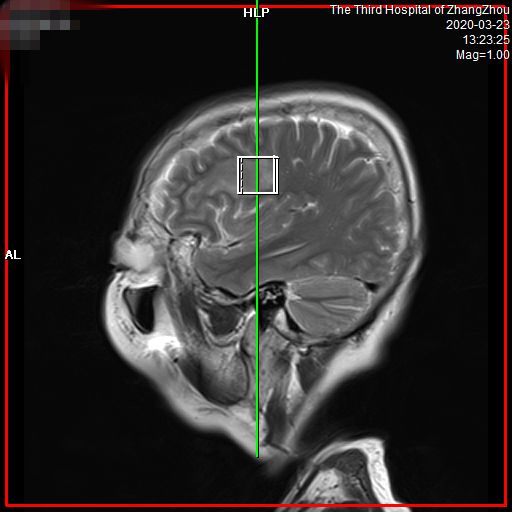

介绍之前,先抛一张我的“帅气照”。

图像更清晰、诊断更精准

• 图像更清晰,病变细节显而易见。对中枢神经系统如头、颈部疾病,以及腹盆部、骨肌系统、乳腺等区域病变检出更敏感,可早发现、早诊断和早治疗。

• 信噪比高,能更早发现小病灶。有关数据显示,对于各类疾病,特别是神经系统和体部系统疾病,可以提前发现病灶,给患者治疗带来了充分的时间,大大提高了病变的诊断水平,让疾病无处可逃,为广大患者带来福音。